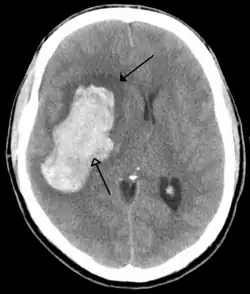

Ictus hemorrágico

Se deben a la rotura de un vaso sanguíneo encefálico debido a un pico hipertensivo o a un aneurisma congénito. Pueden clasificarse en: intraparenquimatosos y hemorragia subaracnoidea.

Las causas más frecuentes en la hemorragia cerebral son la hipertensión arterial y los aneurismas cerebrales.[32]

La hemorragia conduce a ictus a través de dos mecanismos. Por una parte, priva de riego al área cerebral dependiente de esa arteria, pero por otra parte, la sangre extravasada ejerce compresión sobre las estructuras cerebrales, incluidos otros vasos sanguíneos, lo que aumenta el área afectada. Ulteriormente, debido a las diferencias de presión osmótica, el hematoma producido atrae líquido plasmático, con lo que aumenta nuevamente el efecto compresivo local. Es por este mecanismo por lo que la valoración de la gravedad y el pronóstico médico de una hemorragia cerebral se demora 24 a 48 horas hasta la total definición del área afectada.